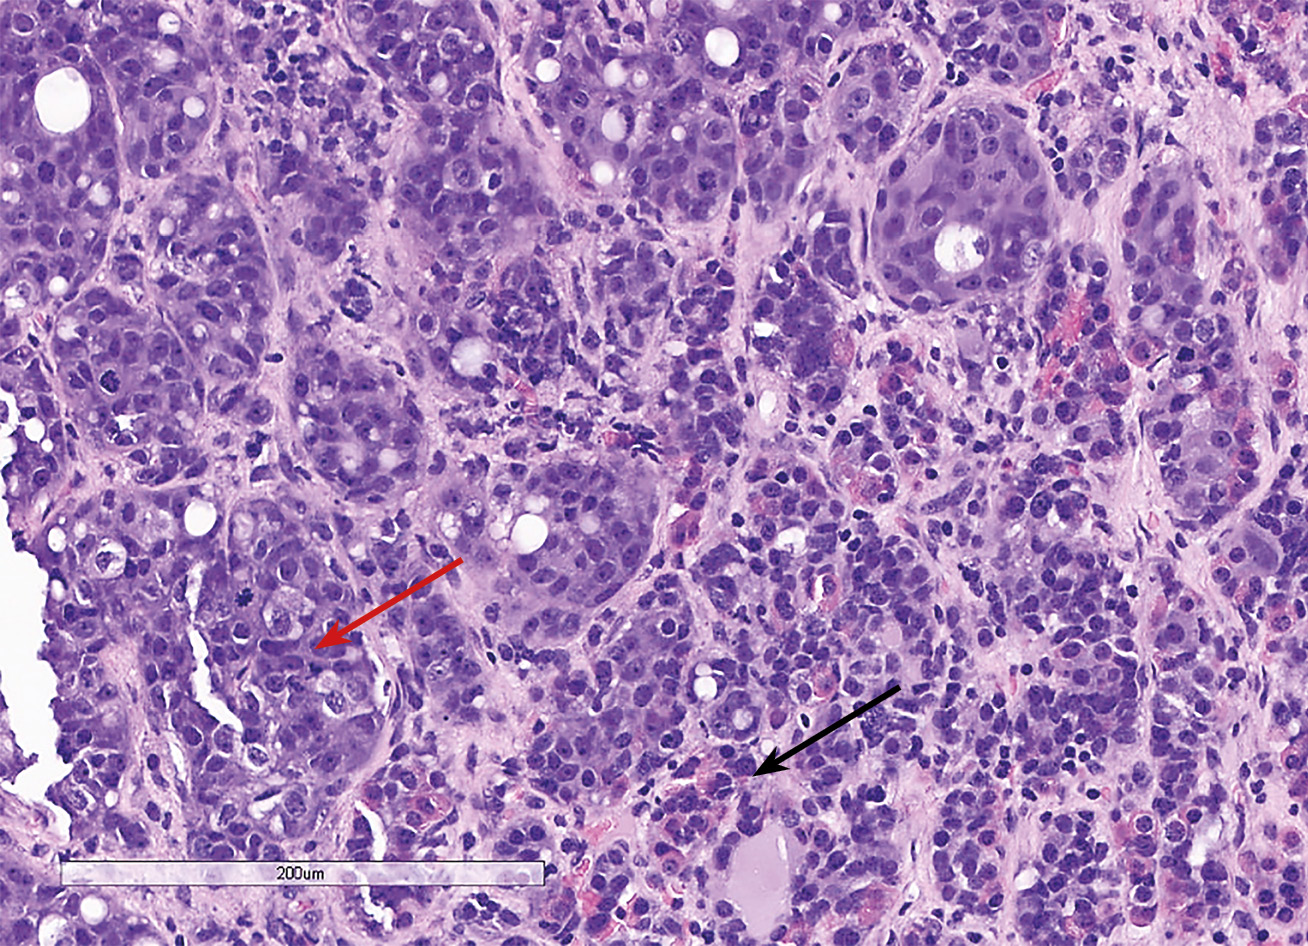

С октября 2020 г. стала отмечать ухудшение общего самочувствия в виде сухости, жжения и покраснения в глазах, спустя время отметила двоение в глазах, появились головные боли преимущественно в теменной области. Выполнено МРТ головного мозга в ноябре 2020 г., в хиазмально-селлярной области выявлено кистозно-солидное объемное образование размерами 22х23х13 мм с компрессией хиазмы, умеренной деформацией зрительных трактов; деформирует дно третьего желудочка, требуется проведение дифференциальной диагностики с краниофарингиомой, однако ранее по МРТ головного мозга от августа 2019 г. образование не визуализировалось (рис. 1.1). При госпитализации в ГНЦ ФГБУ «НМИЦ эндокринологии» Минздрава в декабре 2020 г. у пациентки подтвержден гипопитуитаризм: вторичная надпочечниковая недостаточность (кортизол утром — 96,16 нмоль/л (171–536), АКТГ утром — 13,86 пг/мл (7,2–63,3)), вторичный гипотиреоз (ТТГ — 1,59 мМЕ/л (0,25–3,5), свТ4 — менее 5,15 пмоль/л (9–19)), гипогонадотропный гипогонадизм (ФСГ — 2,21 Ед/л (1,9–11,7), ЛГ — 0,22 Ед/л (2,6–12,1), эстрадиол — 58,07 пмоль/л (97–592)). Данных за гормональную активность образования (пролактин — 263,5 мЕд/л (64–395), ИФР-1 — 199,45 нг/мл (78–311) и нарушение функции нейрогипофиза не получено. При осмотре офтальмологом выявлена частичная атрофия зрительных нервов, при периметрии сужение полей зрения не зафиксировано. Проведено МСКТ органов грудной клетки, очаговых и инфильтративных изменений в паренхиме легких не определяется. Ранее, в ноябре 2020 г., проводилась сцинтиграфия костей всего тела, визуализировалось избыточное накопление индикатора в области правой половины тела L1, пациентка на момент поступления получала золедроновую кислоту по 4 мг в/в 1 раз в 1,5 месяца. В отделении инициирована терапия гидрокортизоном, левотироксином, в связи с раком молочной железы, от назначения менопаузальной гормональной терапии принято решение воздержаться. В связи с развитием масс-эффекта опухоли (головные боли, снижение зрения) пациентке выполнено трансназальное транссфеноидальное хирургическое вмешательство в декабре 2020 г. В операционном материале среди ткани аденогипофиза имелись участки опухоли в виде гнезд и кластеров (рис. 1.2), при иммуногистохимическом исследовании клетки опухоли негативны к транскрипционным факторам гипофиза, гормонам гипофиза, эстрогеновым и прогестероновым рецепторам, позитивные к цитокератину 7 (рис. 1.3, 1.4). Т.е. гистологическая картина и иммунофенотип соответствовали метастазу неспецифицированного рака молочной железы.

Рисунок 1.2. Окраска гематоксилином и эозином.

Среди элементов опухоли (красная стрелка) определяются фокусы аденогипофиза (черная стрелка).